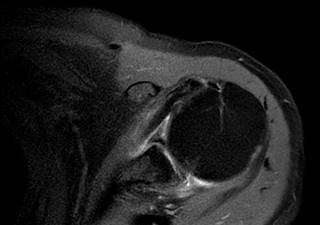

Figura 1: Resonancia magnética de hombro izquierdo en adquisición axial T2 con saturación grasa donde se observa el origen a nivel de la cabeza del húmero del tendón de la porción larga del bíceps.

En un breve repaso anatómico, la porción corta del músculo bíceps braquial dos cabezas se origina del proceso coracoides y la porción larga se origina del tubérculo supraglenoideo, de la región anterosuperior del labrum en la glenoides recorriendo sobre la cabeza del húmero, por último descendiendo por la escotadura bicipital insertándose en la tuberosidad del radio (Figura 1).2,3 La inervación del músculo braquial en ambas porciones es a través del nervio musculocutáneo de las ramas con origen a nivel de C5 y C6. La vascularidad se realiza a partir de ramas de la arteria humeral y bicipitales. Su función principal es flexión del antebrazo a nivel del codo, flexor accesorio del brazo a nivel de la articulación glenohumeral, contribuyendo a la estabilidad en ésta última.2